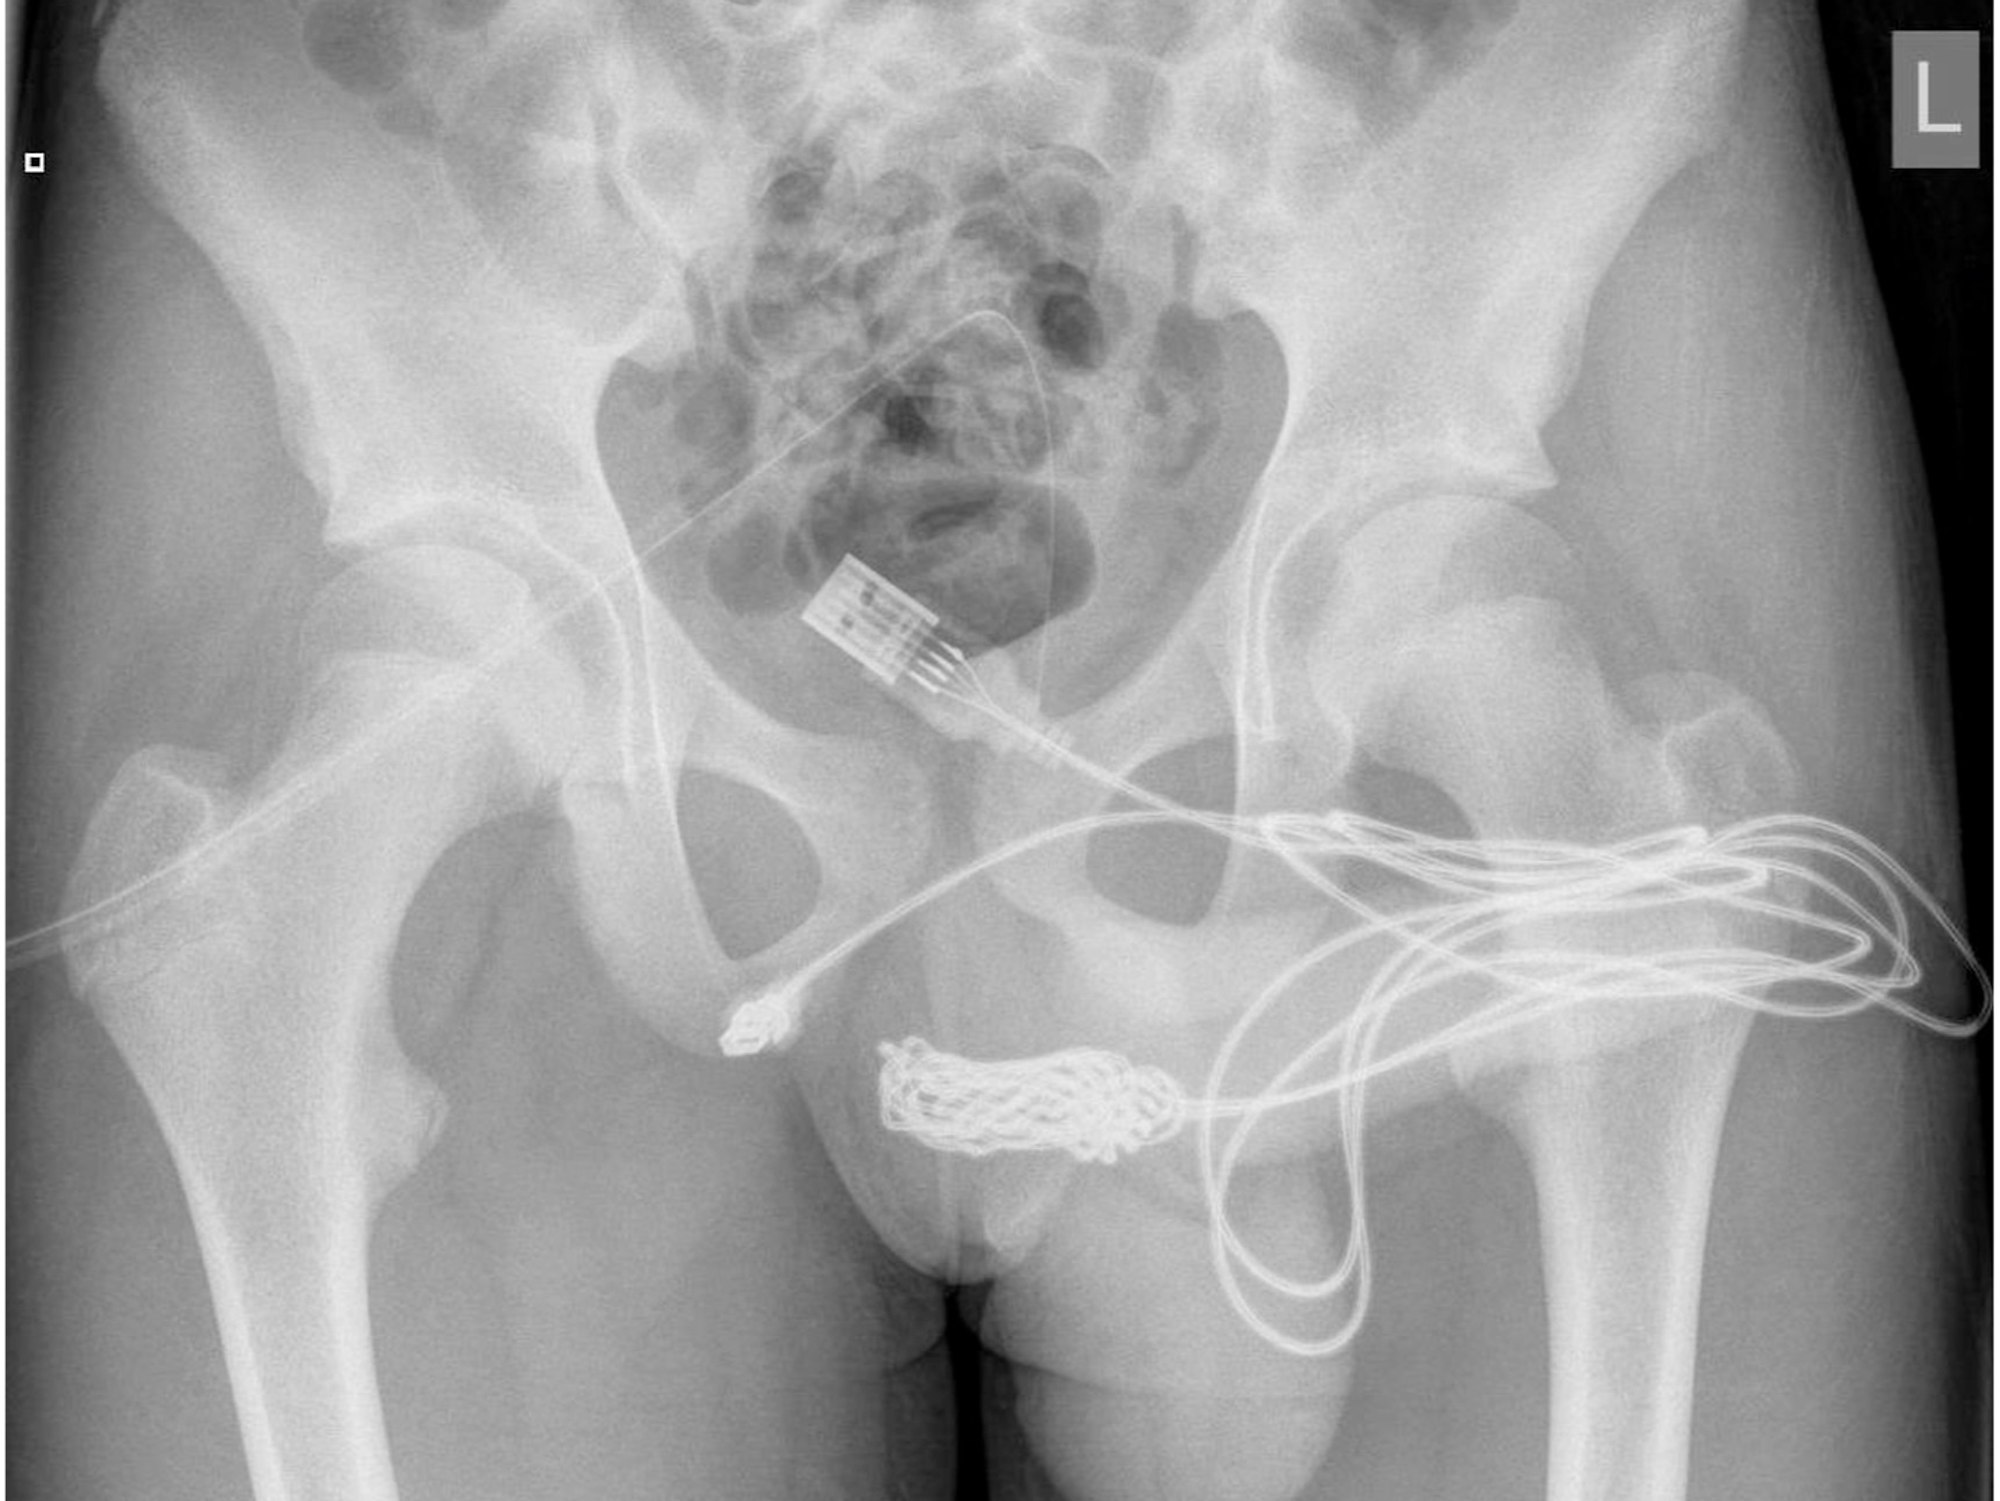

Auf dem Röntgenbild ist deutlich das verknotete USB-Kabel zu sehen, das im Körper des Jugendlichen stecken geblieben war. Der Teenager führte es bei einem fehlgeschlagenen sexuellen Experiment in seinen Penis ein.

Die unglaublichen Röntgenaufnahmen und ein medizinischer Bericht zu dem skurrilen Fall des Jugendlichen wurden jetzt in dem Fachmagazin „Urology Case Reports“ veröffentlicht.

Dort wurde er gründlich untersucht, es wurden Röntgenaufnahmen erstellt, er musste sich einer Blasenspiegelung unterziehen. Anschließend versuchten die Ärzte das Kabel herauszuziehen, allerdings scheiterten zunächst auch die Mediziner. Im Kabel hatte sich ein Knoten gebildet.

Der junge Mann kam um einen chirurgischen Eingriff nicht herum: Dem 15-Jährigen musste ein Muskel im Bereich der Geschlechtsorgane längs aufgeschnitten werden, um an das Kabel zu gelangen. Anschließend wurde das Kabel abgeschnitten, beide Enden konnten erfolgreich durch die Harnröhre herausgezogen werden.